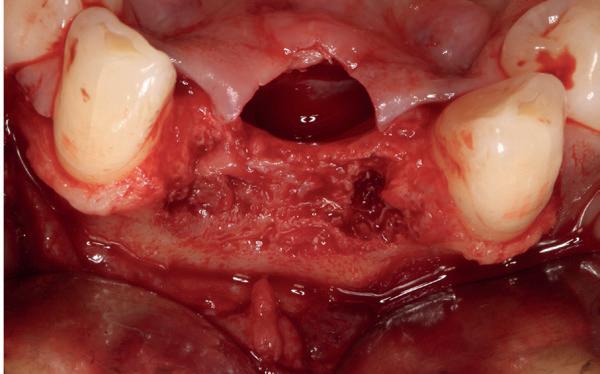

• Intra-orale scan voor studiemodellen, proefopstelling en beoordelen ruimte palatinaal

Vervaardigen essix retainer met dummies waarbij er een emergence profile van de 11 en 21 werd gevormd door eivormige dummies 4 mm in de gingiva te plaatsen

• Aanvulling zachte weefsels met de VISTA techniek en een vrij gingivatransplantaat uit het palatum links en direct dragen van de essix retainer

Na 4 weken intra-orale scan voor de etsbrug en kleurbepaling bij de technicus

• Plaatsen van de etsbrug met een composietcement

Voordat er gescand kon worden voor een etsbrug, werd een studiemodel vervaardigd om met de technicus te overleggen of er voldoende ruimte was voor 2 centrale incisieven in de mesio-distale zin en of er voldoende ruimte was in occlusie voor de vleugels van de etsbrug. Er hoeft enkel nog aan de 12 en 22 pala-

tinaal geslepen te worden als er geen 1,5 mm ruimte voor de vleugels behaald kan worden. De ruimte was op de dunste plekken 1 mm, dus een kleine preparatie in de 12 en 22 palatinaal was nodig. Omdat de kaak volledig afgevlakt was en dun was geworden, kunnen de dummies van de etsbrug enkel op de kaak “gelegd worden”, maar daarbij zijn er geen papillen en staat de cervicale rand van de dummies net voor de kaak. Een esthetisch resultaat kan daarmee niet behaald worden. Daarom is een aanvulling van de zachte weefsels in de breedte nodig, als het creëren van een emergence profile, waarbij het oogst alsof de gebitselementen uit het weefsel vertrekken.

Voor de aanvulling zachte weefsels chirurgie werd gekozen voor de VISTA techniek, hierbij worden er twee incisies partial thickness flap hoog in de mucosa gemaakt, waarna er ruimte vanuit de incisies wordt getunneld tussen de gingiva en het periost door middel van VISTA tunnel instrumenten. Uit het palatum links werd een vrij gingivatransplantaat geoogst van 15x10 mm met een dikte van 3 mm, die voor inhechten werd geëpithelialiseerd. Als het epitheel niet wordt verwijderd, kan deze graft door

de mucosa heen groeien, dat ten koste gaat van de esthetiek. In het donorgebied wordt een collageen spons ingehecht, waardoor de patiënt daar minder last van heeft. Het bindweefsel wordt door de hul-

pincisies met hechtingen naar het buccale en coronale deel getrokken en aldaar ingehecht. Met twee incisies werd ook de emergence profile gecreëerd (afbeelding 6-13). Voor een goede genezing van het